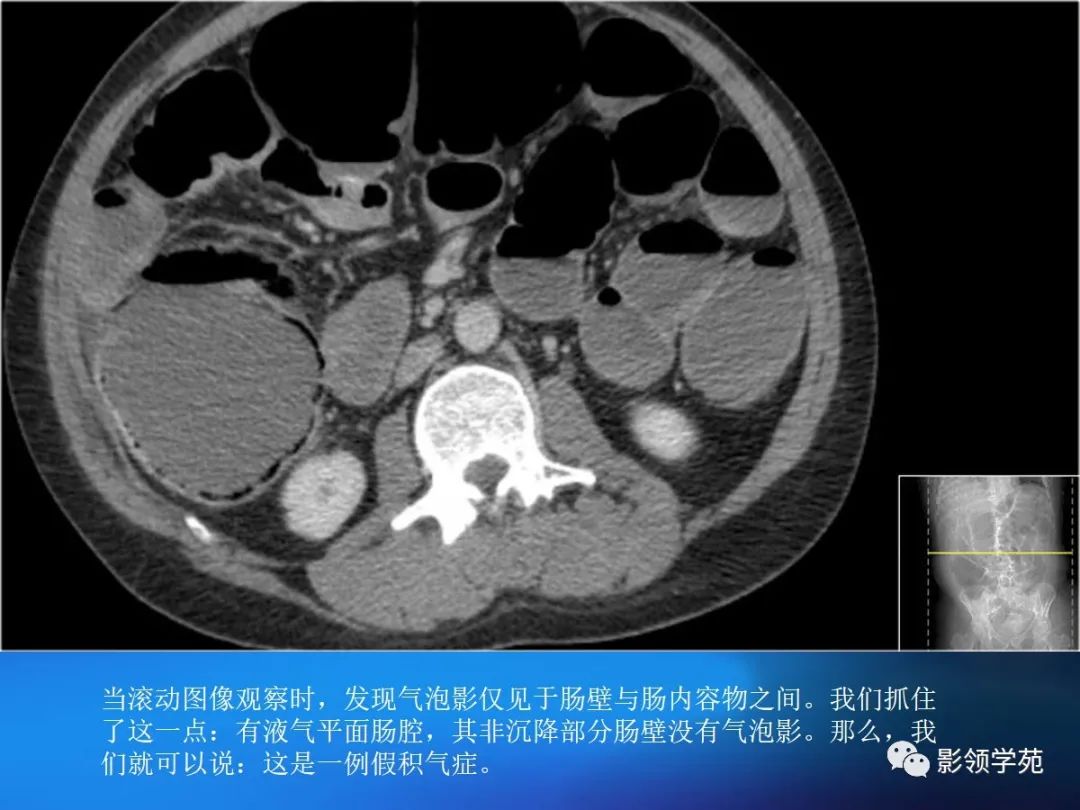

目前尚缺乏统一标准,一般认为,排除肠管充盈不佳或肠壁收缩时导致的假象后,当肠壁大于3mm是即考虑增厚。